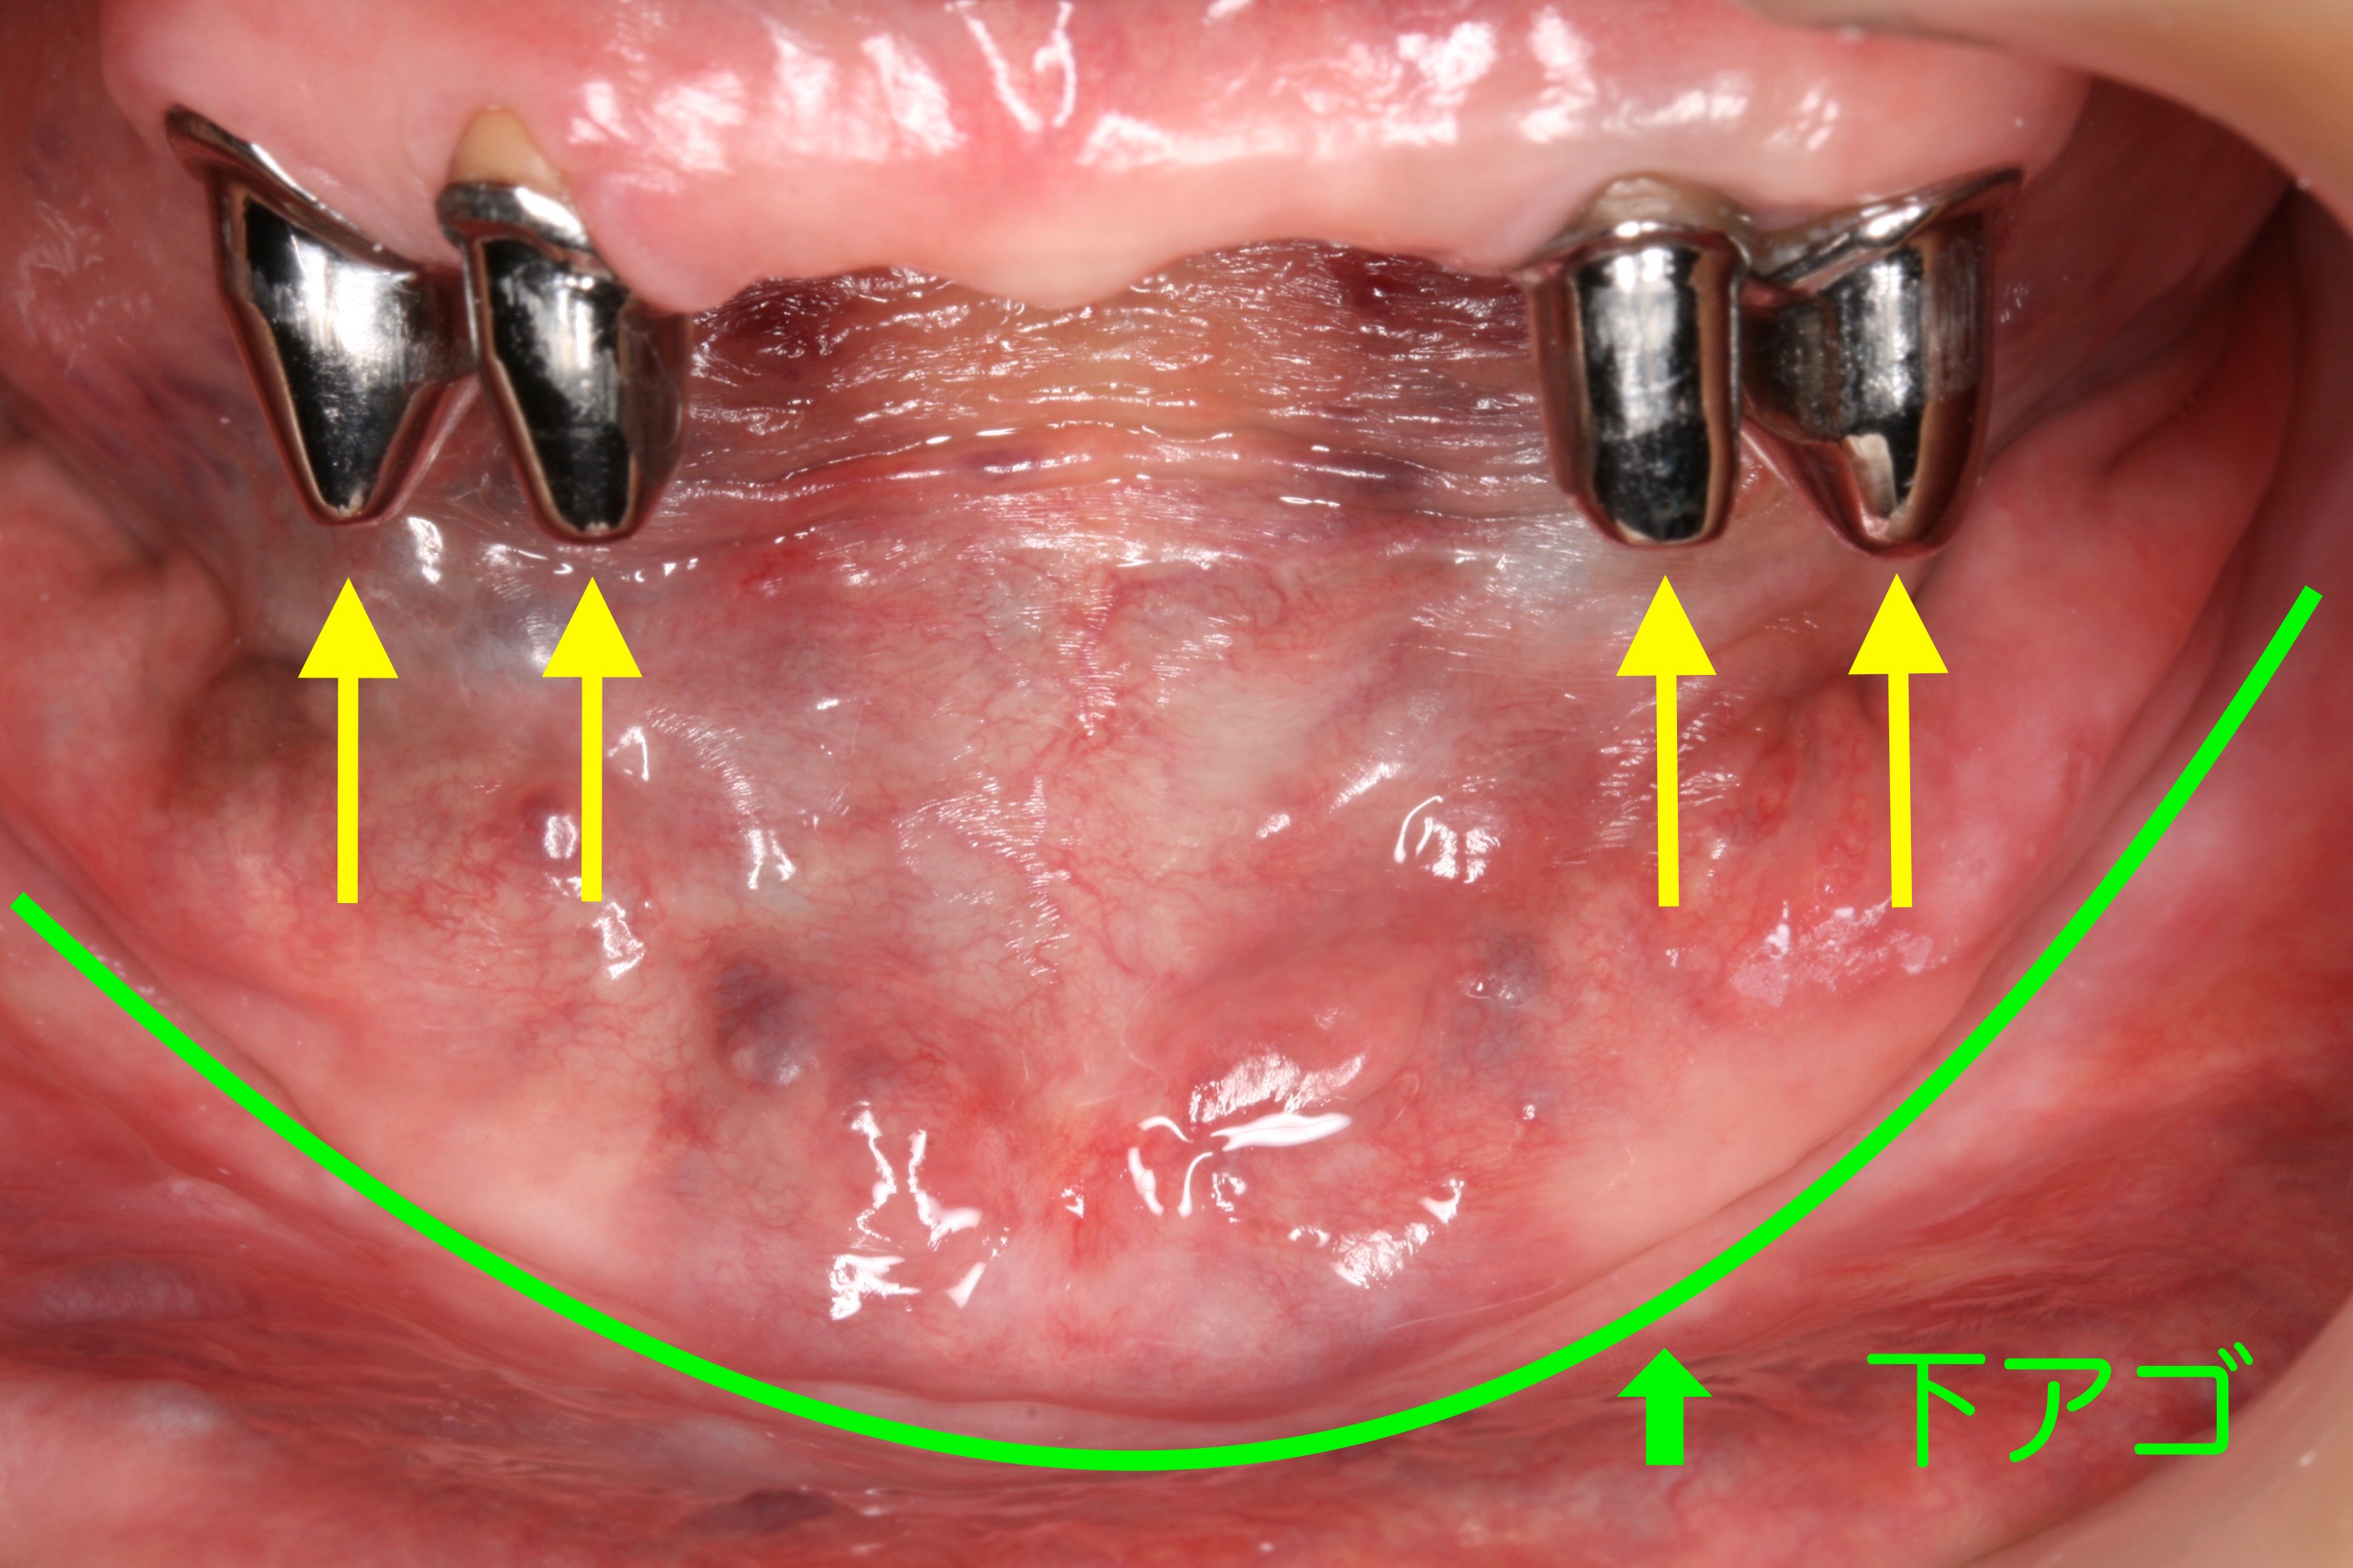

ケース NO.1 ⬆︎ 残した歯 ⬆︎ 抜いた歯

上が総入れ歯、下がレジリエンツテレスコープ義歯です。